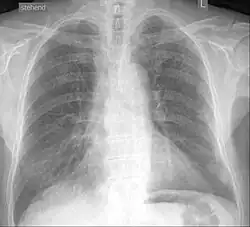

Röntgenaufnahme eines an Silikose erkrankten Mannes

Die Silikose (von lateinisch silex [Genitiv silicis] „Kiesel, harter Stein“) oder Quarzstaublunge ist eine sogenannte Pneumokoniose (Staublunge). Sie wird durch das Einatmen von Feinstaub mit α-Quarz oder einer anderen kristallinen Modifikation des Siliciumdioxids hervorgerufen, die zu einer Lungenfibrose führt.[1]